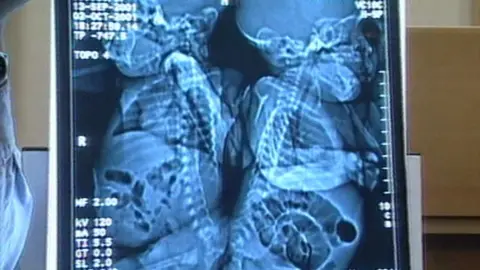

Birmingham Children’s HospitalThe operation Sanchia and Eman needed to divide their spinal cords, which were fused at the base, had never been carried out in the UK.

Medics led by neurosurgeon Tony Hockley apportioned the spinal cord and separated some major organs, including their bladders.

Describing the procedure afterwards, Mr Hockley told The Guardian: “The two came together and fused as one. There was also a degree of rotation. We had to make our cut so that each baby girl got her spinal cord back, and make a tube to cover it.

“The technique of cutting is conventional but it is knowing where to cut. We had nerve stimulators to help.”

After the separation of the spine, paediatric surgeon Peter Gornall and one of the world’s leading experts on conjoined twins, Lewis Spitz from Great Ormond Street, carried out the careful splitting of some of the girls’ organs, which were whole but were stuck together.